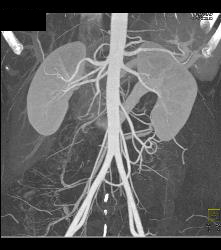

Retroaortic Left Renal Vein